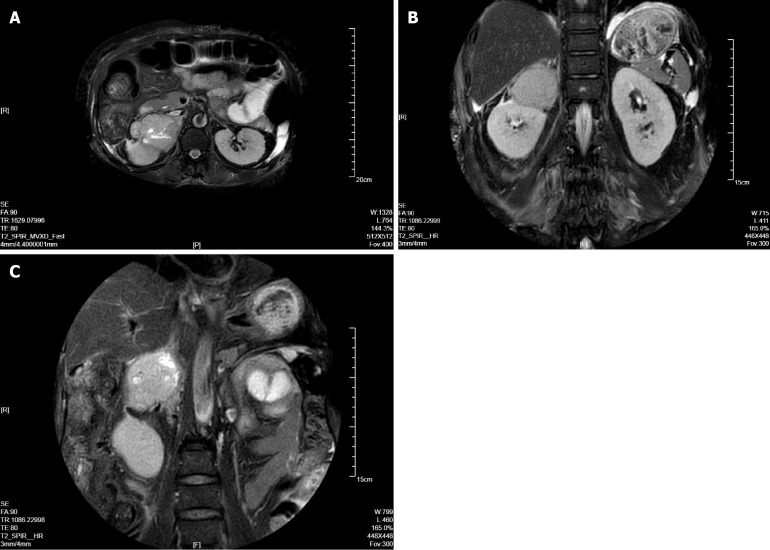

Case summary: A 53-year-old female presented predominantly with persistent and refractory vomiting as her chief complaint, accompanied by signs of acute heart failure [left ventricular ejection fraction (LVEF) 30%]. Initial evaluation at a primary hospital, including coronary angiography (revealing only mild stenosis), led to a misdiagnosis of coronary artery disease. Despite standard anti-thrombotic, anti-heart failure, and anti-emetic therapy, her vomiting persisted and heart failure did not resolve. Subsequent hospitalization revealed dramatic paroxysmal hypertension (202/129 mmHg to 97/51 mmHg) and fever. Significantly elevated plasma metanephrines and normetanephrine, combined with abdominal computed tomography and magnetic resonance imaging, confirmed a right adrenal pheochromocytoma. This diagnosis was significantly delayed due to the atypical prominence of gastrointestinal symptoms masking the underlying endocrine crisis.